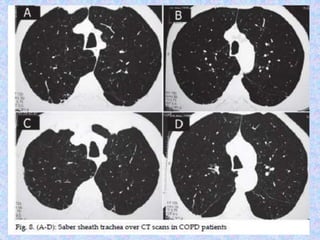

On the lateral radiograph, a "barrel chest" with widened anterior-posterior

diameter may be visualized. The "saber-sheath trachea" sign refers to marked

coronal narrowing of the intrathoracic trachea (frontal view) with concomitant

sagittal widening (lateral view).

Abnormal chest X-rayfindings are usually not seen until COPD is severe. In this case, the X-ray may show: Flattening of the diaphragm, the large muscle that separates the lungs and heart from the abdominal cavity. Increased size of the chest, as measured from front to back. A long narrow heart. Abnormal air collections within the lung (focal bullae). On the lateral radiograph, a "barrel chest" with widened anterior-posterior diameter may be visualized. The "saber-sheath trachea" sign refers to marked coronal narrowing of the intrathoracic trachea (frontal view) with concomitant sagittal widening (lateral view). CT finding in emphysema is diagnosed by alveolar septal destruction and airspace enlargement, which may occur in a variety of distributions. Centrilobular emphysema is predominantly seen in the upper lobes with panlobular emphysema predominating in the lower lobes. Paraseptal emphysema tends to occur near lung fissures and pleura. Formation of giant bullae may lead to compression of mediastinal structures, while rupture of pleural blebs may produce spontaneous pneumothorax / pneumomediastinum.